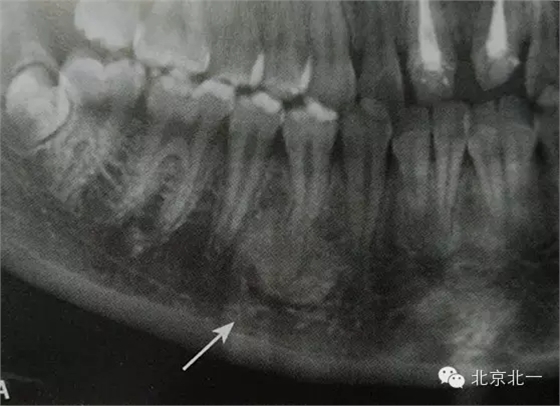

【CBCT表現(xiàn)】:

在CBCT上,根尖型骨島無(wú)低密度帶狀影包繞,與周圍骨質(zhì)分界清晰,具有特征性的毛刷樣邊緣,且其發(fā)生區(qū)域的牙根牙周膜影像連續(xù)、完整、不導(dǎo)致頜骨的膨隆。

右下頜C4根尖區(qū)課件一類圓形高密度影,與周圍骨質(zhì)分界清晰,C4牙周膜影像連續(xù)、完整,下頜骨未見(jiàn)膨隆。